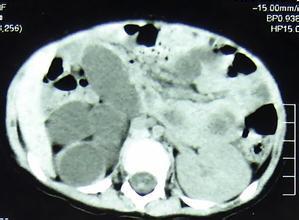

超音波、CT、MRI檢查可明確區分增大的腎是積水還是實性腫塊亦可發現壓迫泌尿系統的病變,由於超聲檢查已經普及且為無創傷性,可以在尿路造影以前進行。放射性核素掃描和腎圖亦可用於腎積水的診斷。對動力性梗阻病例,可在尿路造影是觀察腎盂、輸尿管蠕動及排空情況。神經原性膀胱可見膀胱造影形似"寶塔",有成小梁和假性憩室。

發燒是小孩常有的現象,可是有時並不是感冒造成的;泌尿道感染也同樣會有輕微的發燒現象,卻常常被誤診為感冒。值得注意的是,輕微的泌尿道感染吃感冒藥,是可以暫時控制下來,可是如果患有潛藏的疾病,泌尿道仍會再發生感染,而引起發燒。曾有一位七歲的小男孩,從小就常有輕微的發燒,偶爾有輕微腹痛的情形,都被當作是普通的感冒治療,平常也沒有出現什麼特別的症狀。有一次小男孩卻一連三天高燒不退,到醫院用超音波一照,原來是右邊腎臟積水非常的嚴重,進一 步用電腦斷層檢查,才發現小男孩右邊的腎臟幾乎都壞死,甚至到了必須切除的地步。